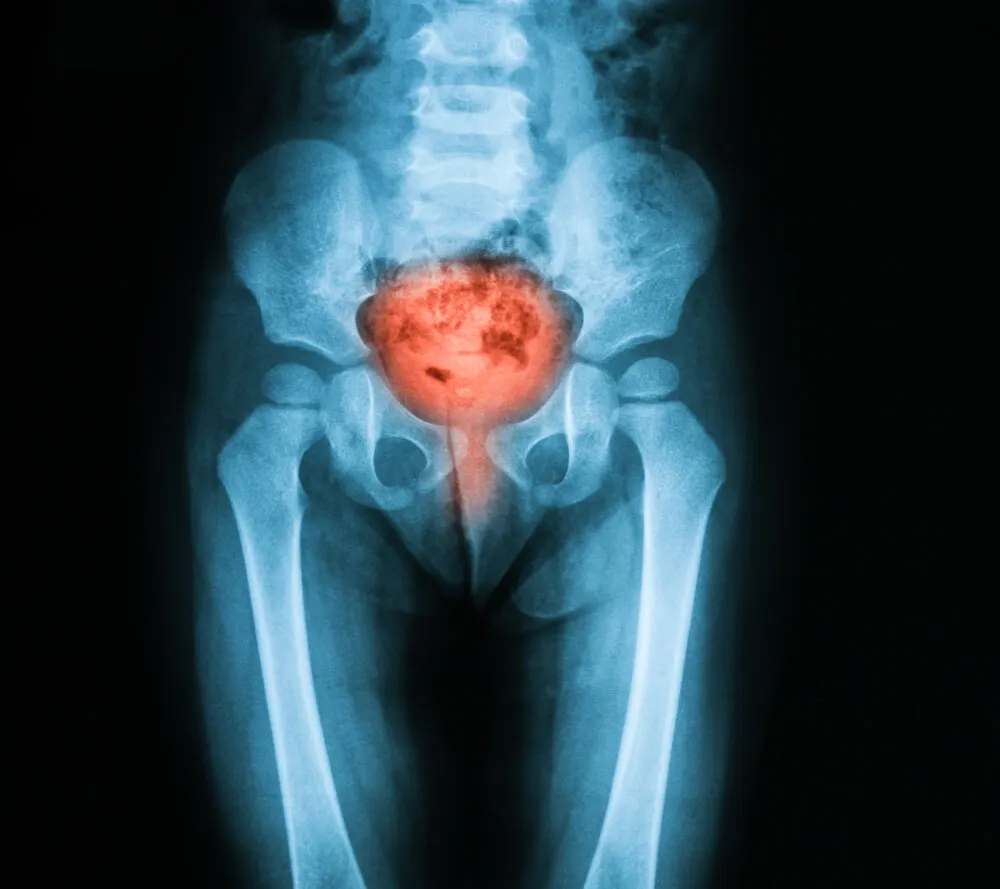

- Diagnostiquer les maladies de la vessie ou de l’urètre. Des conditions telles que la cystite, les calculs, le cancer, etc. sont incluses.

- Rechercher les causes de certains signes ou symptômes. La cystoscopie peut aider à établir la cause de problèmes tels que l’incontinence, une miction douloureuse, une vessie hyperactive et une hématurie, ou du sang dans les urines.